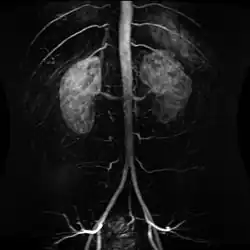

Contrast enhanced MRA of the abdominal aorta demonstrating normal paired arteries. Contrast enhanced MRA of the abdominal aorta demonstrating normal paired arteries.